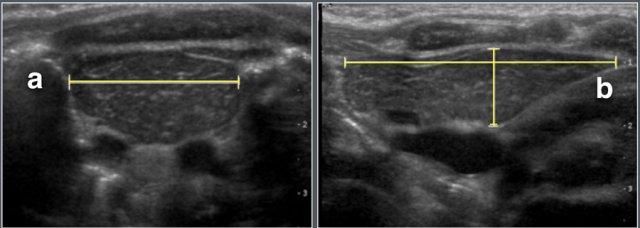

Đo chiều dài thận trên siêu âm.

Kích thước đầu-đuôi của mỗi thận được đo bằng siêu âm tiêu chuẩn.

Đo chiều dài thận sơ sinh trên siêu âm.

Trung bình, thận trái dài hơn thận phải 1,9 mm.